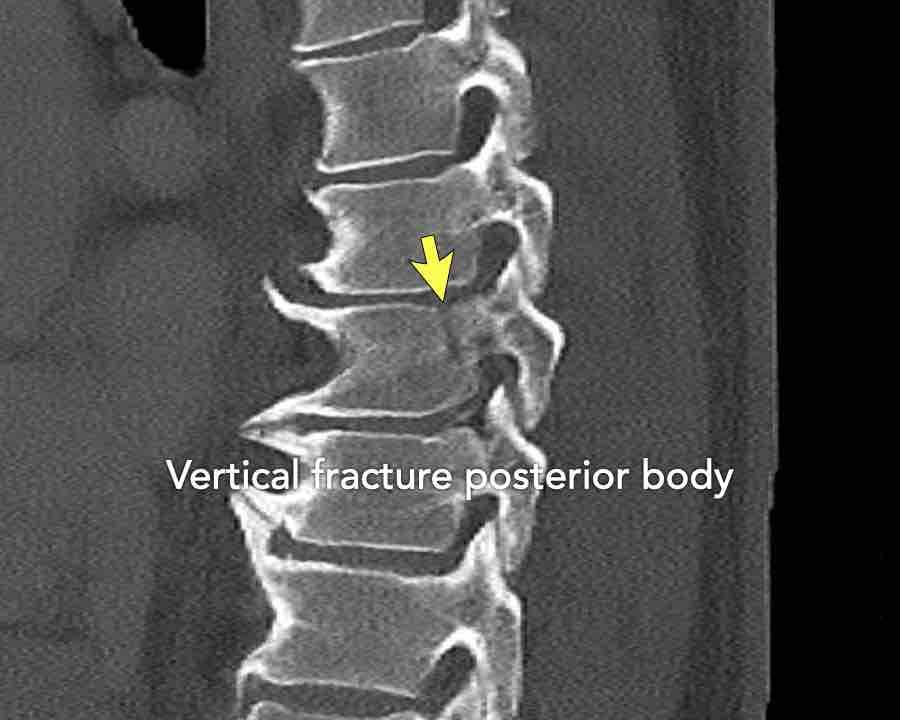

A3 Incomplete Burst fractures

Fracture with any involvement of the posterior wall; only a single endplate fractured.

A vertical fracture of the lamina is usually present and does not constitute a tension band failure.

What is the AO-type of the vertebral body fracture based on only these two inages?

Findings:

- Fractures of the vertebral body with involvement of upper endplates (1 points) and posterior wall (2 points)

- Bulging of the posterior wall without any other signs of dislocation is the result of the burst fracture.

Therefore no C injury.

Conclusion

Injury type A3